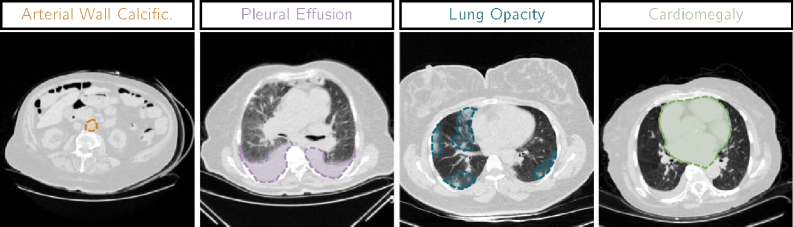

Computed Tomography (CT) provides detailed imaging of the human body, enabling radiologists to thoroughly examine various anatomical regions, identify abnormalities, and guide patient care from initial diagnosis to follow-up [mazonakis_computed_2016]. However, the growing number of CT scans [broder_increasing_2006] and the associated workload for radiologists have created a pressing need for automated methods to assist in analyzing these volumes [chen_recent_2022]. In medical imaging, and particularly in CT scans, substantial progress has been made in leveraging deep learning techniques to support radiologists in tasks such as segmentation [gu_convformer_2022], image restoration [yuan_deep_2023], classification [draelos_machine-learning-based_2021], and more recently, report generation [hamamci_ct2rep_2024]. As illustrated in Figure 1, multi-label anomaly classification from Three-Dimensional (3D) CT volumes remains a challenging task due to the significant variability in the anomalies that need to be detected.

Refer to caption

Figure 1: Examples of 4 axial CT scan slices with anomalies of varying sizes from the CT-RATE dataset.